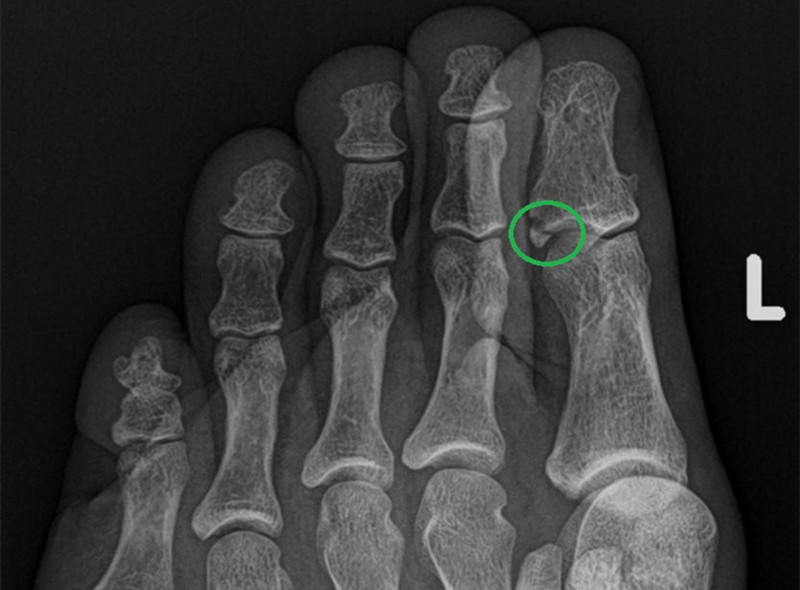

中到重度的扭伤可能和骨折难以分辨,都会出现肿胀、淤青,脚趾难以移动,站立和行走困难。尤其 撕脱性骨折 和应力性骨折,没有明显的外伤,容易和扭伤混淆。 撕脱性骨折是指一小块骨片被肌肉或者韧带从骨头上撕下来, 会出现肿胀、瘀伤以及脚趾关节活动困难。有时可能被误诊为扭伤,甚至采取了错误的治疗。

应力性骨折则是由于重复运动、经常负重、维生素D缺乏、营养不良或骨质疏松症引起的,没有明显的外伤,也容易被当做扭伤,患者可能认为只是一件小事,同时在骨折后两到四个星期内,影像学检查可能发现不了应力性骨折。如果不及时治疗,应力性骨折会越来越疼,并对骨头造成更严重的损害。

虽然以上内容有利于区别扭伤和骨折,但万无一失的判断办法还是及时就医,医生会询问症状以及疼痛的程度。如果怀疑骨折,就要进行影像学检查。最常见的骨折检查是X光和CT检查,医生会从多个角度观察骨骼的情况。出现以下情况,要引起警惕: